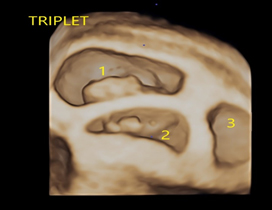

A multiple pregnancy is one in which the mother carries more than one baby in her womb. Most commonly is it two called as twins. If there are three, it is called as triplet and if four, it is quadruplet pregnancy..

• Early viability scan- this scan is to determine the number of fetuses and type of multiple pregnancy, that is to determine the CHORIONICITY.

• First trimester screening- at 11-13+6weeks- Here, we determine the number of fetuses, type of multiple pregnancy, dating, structural abnormalities and screen for chromosomal abnormalities.

• Anomaly scan -done between 18-20 weeks- to do detailed evaluation of the structural abnormalities of the babies.